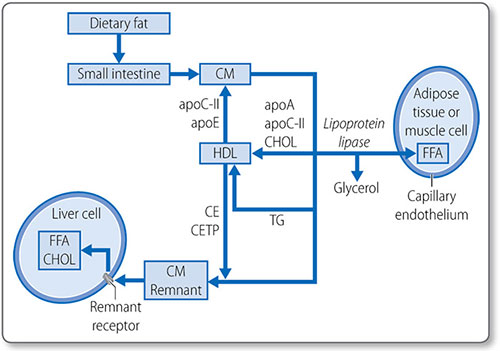

Cholesterol metabolism

Cholesterol is a 27-carbon steroid alcohol (sterol) lipid (Figure 1.45). It is a key component of cell membranes, allowing their fluid movement, and is the precursor to vitamin D, bile acids and steroid hormones, including testosterone and cortisol.

Cholesterol is consumed in the diet and synthesized de novo in the liver and intestine. On average, 800 mg of cholesterol is synthesized daily in a person on a low-cholesterol diet.